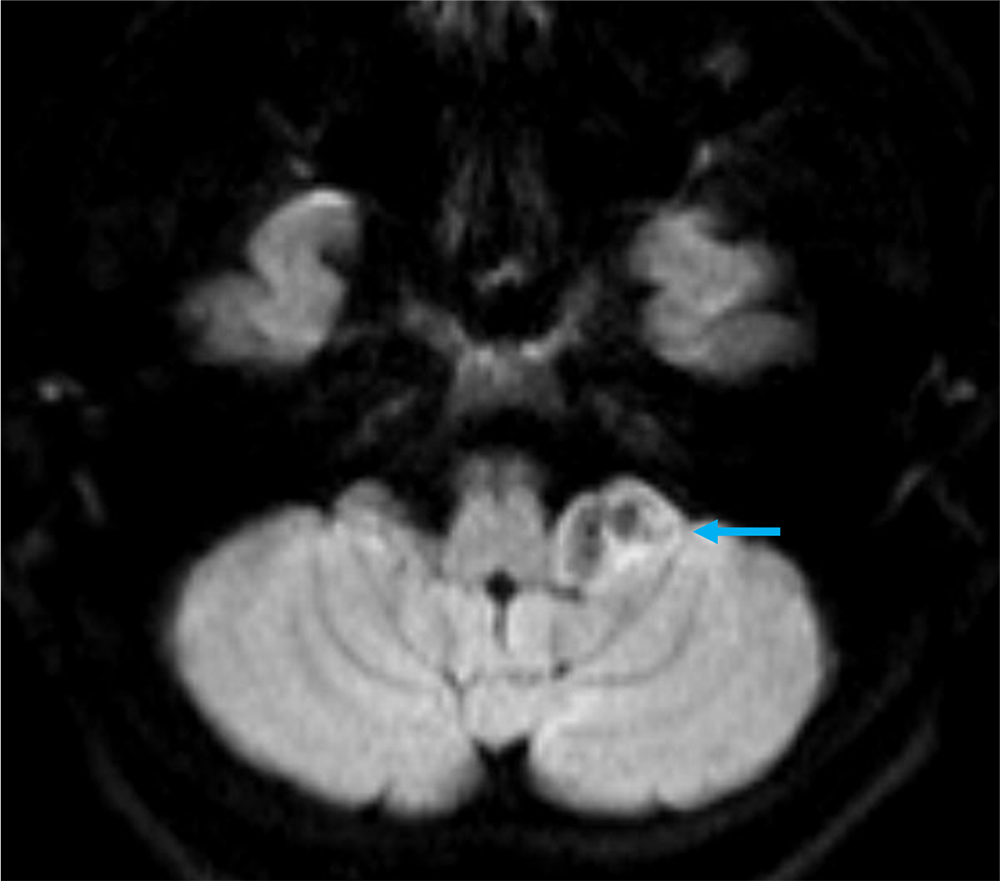

40歳代、女性、55kg、pilocytic astrocytoma

2か月前から頭重感および嘔気が持続しており、他院の単純CTにて左小脳腫瘍が疑われた。当院紹介となり、造影MRIが撮影された。

本症例では左小脳延髄角部に嚢胞成分を伴う腫瘍が存在し、左下位脳神経からの発生、もしくは小脳実質内腫瘍の鑑別が重要であった。前者であれば神経鞘腫、後者であればpilocytic astrocytomaの可能性が高くなる。3Dの脂肪抑制T1強調画像を撮影し、小脳実質内の可能性が高く、pilocytic astrocytomaを上位に考えた。手術が施行され、無事に完全摘出され上記の診断となった。

当該疾患の診断における造影MRIの役割

小脳腫瘍の鑑別において、造影MRIは必須である。本症例のように若年者の小脳実質内腫瘍の場合、特に血管芽腫との区別が重要となる。血管芽腫も嚢胞成分を伴う腫瘤を呈することが多いが、充実成分は強い造影効果を呈する。本症例は血管芽腫を疑うような強い造影効果とは言えず、pilocytic astrocytomaを疑うことが可能であった。